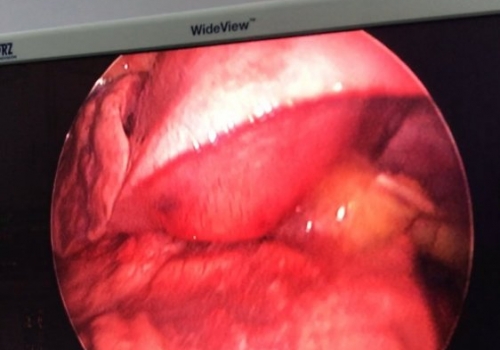

MediastinalTeratoma .Torokoskopik teratomanın eksiziyası

Daha bir çətin əməliyyat 8 yaşlı pasientdə döş boşluğunda törəmə- Ağciyərin orta payı üzərində böyük həcmli törəmə Teratoma. Torokoskopik törəmənin eksiziyası